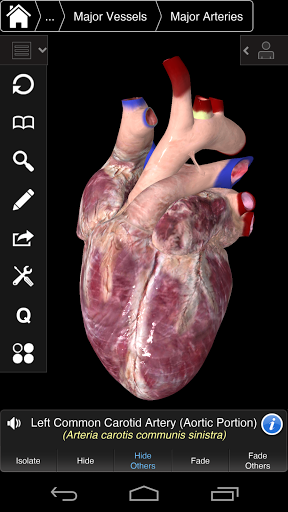

⁃also includes the Brain and Heart

---- Multiple Selection Mode - Hide/Fade/Isolate individual or multiple structures

---- Correct audio pronunciation for every structure

---- Latin nomenclature for each anatomical structure